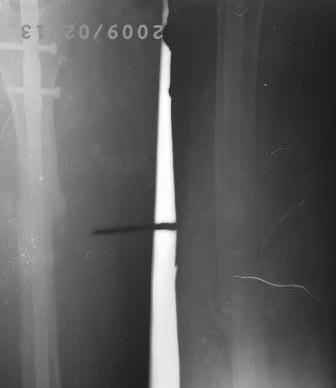

12.02.09г б-ная оперирована: з/остеоклазия (без особого труда- видимо тугой ложный сустав) коррекция деформации, удаление штифта из надвертельной обл, рассверливание канала гибкими развертками, реостеосинтез блокируюшим гвоздем Д-11мм.

Но я впервые почувствовал такую сильно ОСТЕОПОРОТИЧНУЮ кость, что блокируюшие винты проваливаются внутрь кости, что винты можно ввести без сверления кости, и что винты провинчиваются холостую, т.е. не стабильно.

P.S. Снимки не качественные, извиняюсь! последний снимок ЭРГА, два снимка объединил.

Я заранее приношу свои извинения, но по демонстрации видно, что сама методика БИОС использована с нарушениями. Да я с Вами согласен и сам часто встречался подобными случаями, когда из-за отсутствия функции конечности (опорной и двигательной) поврежденный сегмент теряеть минеральную плотность, тем самым развивается остеопороз. Однако Вам надо было заранее учитывать эти моменты и дистальные винты надо было установить четко бикортикально, в Вашем случае верхний дистальный винт короткий, нижний дистальный винт вне отверстия, в таком расположении он никак не может быть в блокирующем отверстии. Ранняя опорная нагрузка зависит от стабильности синтеза, веса пациента, но в любом случае дозированная нагрузка (собственный вес конечности) нужна, иначе срастить ложный сустав и ликвидровать остеопороз невозможно (кость должна выполнять свою функцию). С уважением Ерсин Жунусов.

Гвозди мы закупали из предприятия ЦИТО, и если Вы заметили у них нижнее дистальное отверстие продолговато-овальное, а не круглое, поэтому оно позволяет ввести винт и под углом, конечно это тоже ошибка, ну два последних винта было введено из одного маленького разреза - поэтому так получилось!